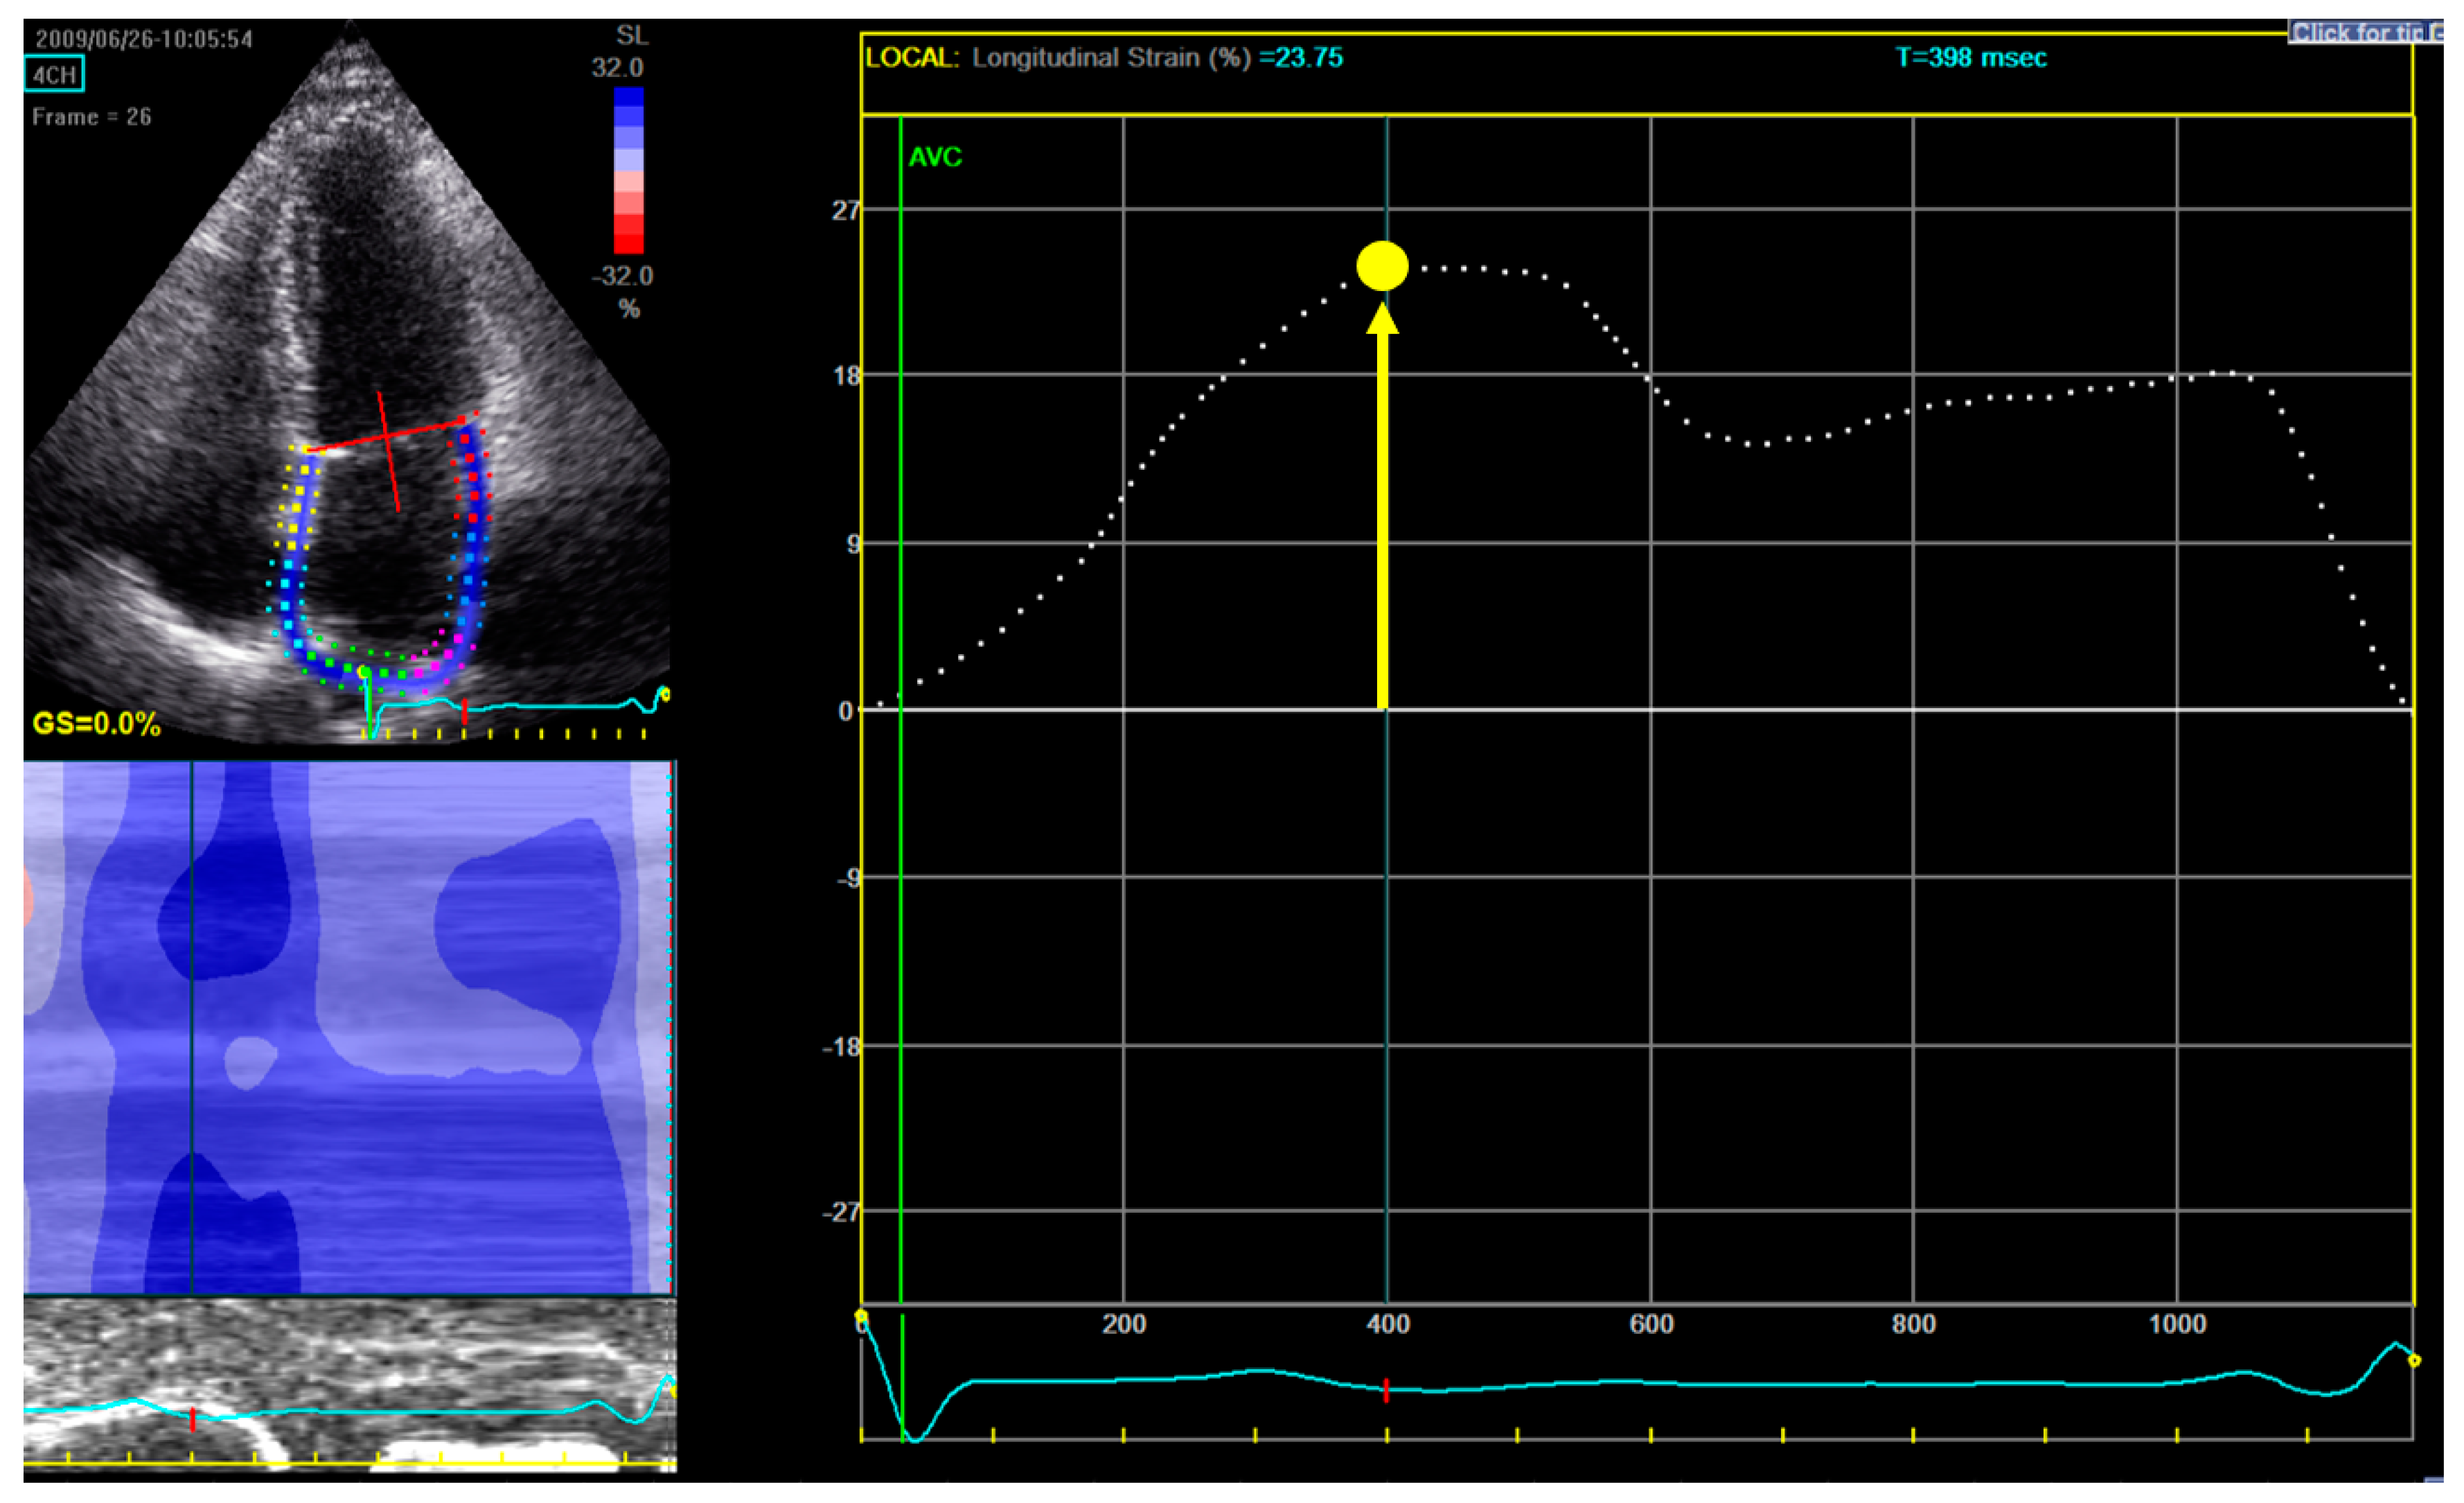

For measuring LA longitudinal strain, a dedicated non-foreshortened apical 4-chamber view was used, and the endocardial border tracing was started at the septal part of the mitral annulus, extrapolated across the pulmonary veins and LA appendage and ended at the opposite mitral annulus side (Figure 1) [16].

Figure 1.

Measurement of left atrial reservoir strain (εR). Upper-left panel shows the selection of the region of interest: in a dedicated non-foreshortened apical 4 chamber view, the tracing begins at the level of the endocardial border of the mitral annulus; it is then continued along the endocardial surface of the left atrium extrapolating across the orifices of the pulmonary veins and left atrial appendage, ending at the opposite side of the mitral annulus. Right panel displays the left atrium longitudinal strain curve: the zero-reference point is at end-diastole and εR is calculated as the difference between the strain value at the mitral valve opening and ventricular end-diastole (positive value). In this example in a patient from our study, εR is 23.75%.

From the LA strain curve, ƐR was measured as the positive peak systolic value within LV end-diastole (mitral valve closure) and mitral valve opening [16]. The zero-reference point was chosen at LV end-diastole (onset of QRS). ƐR was selected as the parameter to assess LA function, since it was shown in previous literature to have the best reproducibility and feasibility (also in atrial fibrillation patients) and the strongest prognostic value [17,18,19].